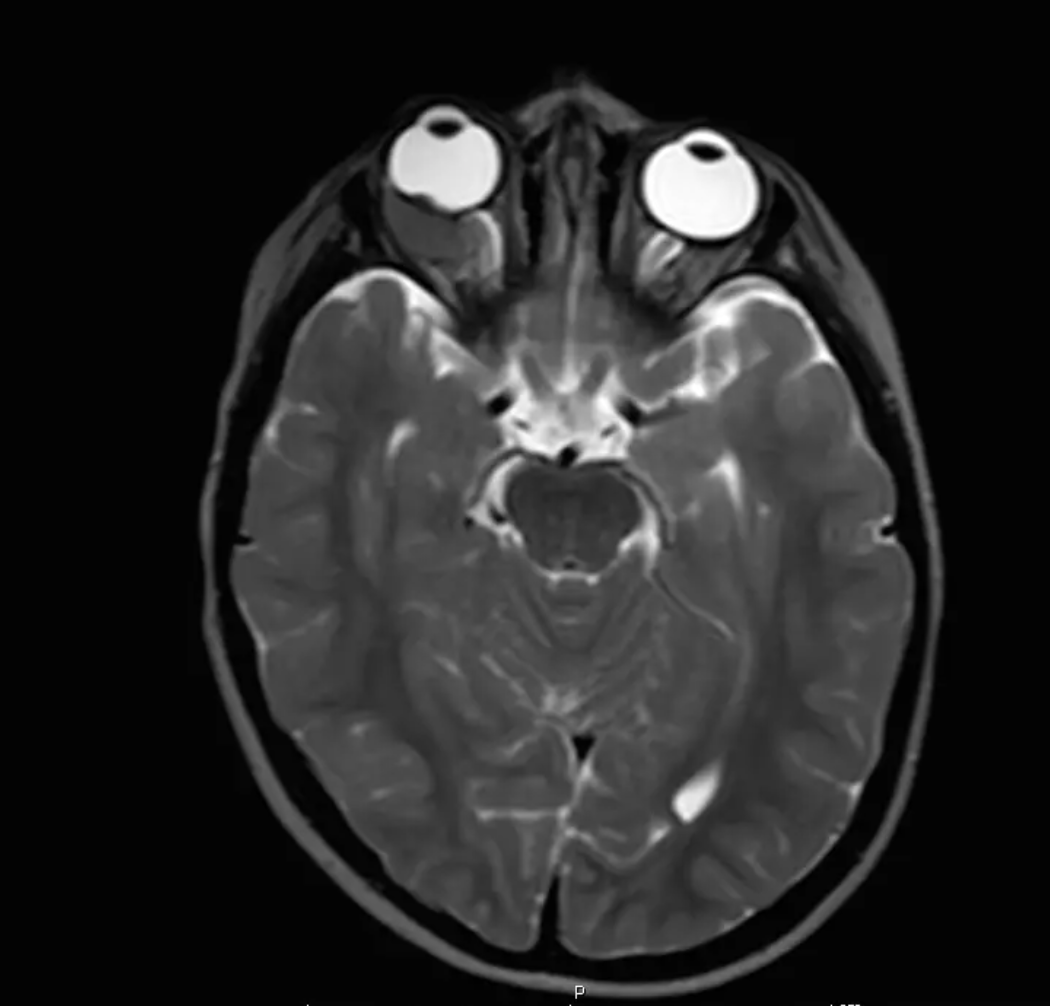

Confirm diagnosis w/exam under anesthesia:

B-scan

MRI